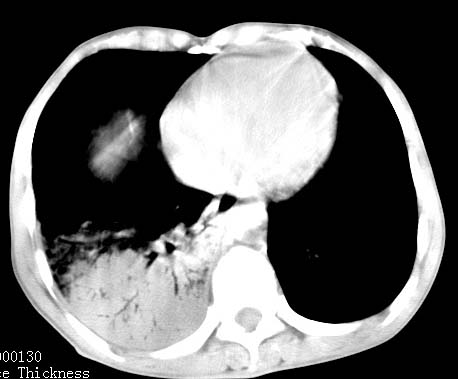

病人女 60岁 咳嗽 气促十余天,大叶性肺炎.

右肺上下叶均见 大片状密度增高影,边界清晰,其内可见支气管充气征,气管支气管通畅。纵膈略向右移位,其内无肿大淋巴结影。首先考虑炎性病变。不排除一些特异性的炎症。不知道发烧吗??wbc高吗??建议治疗后复查!!